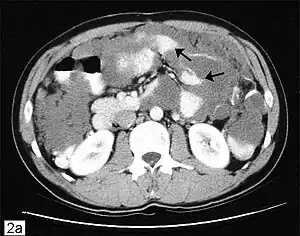

| Computed tomographic scan of an abdomen showing pseudomyxoma peritonei with multiple peritoneal masses (arrow) with "scalloping effect" seen. | |

This disease is often discovered during surgery for other conditions, e.g., hernia repair, following which an experienced pathologist can confirm the diagnosis. Advanced stages may present as tumors palpable on the abdomen or distention of the belly ("jelly belly" is sometimes used as a slang term for the condition). Due to the rarity of this disease, it is important to obtain an accurate diagnosis so that appropriate treatment may be obtained from a Gastro intestinal cancer surgeon. Diagnostic tests may include CT scans, examination of tissue samples obtained through laparoscopy, and the evaluation of tumor markers. In most cases a colonoscopy is unsuitable as a diagnostic tool because in most cases appendix cancer invades the abdominal cavity but not the colon (however, spread inside the colon is occasionally reported). PET scans may be used to evaluate high-grade mucinous adenocarcinoma, but this test is not reliable for detecting low-grade tumors because those do not take up the dye which shows up on scans. New MRI procedures are being developed for disease monitoring, but standard MRIs are not typically used as a diagnostic tool. Diagnosis is confirmed through pathology.